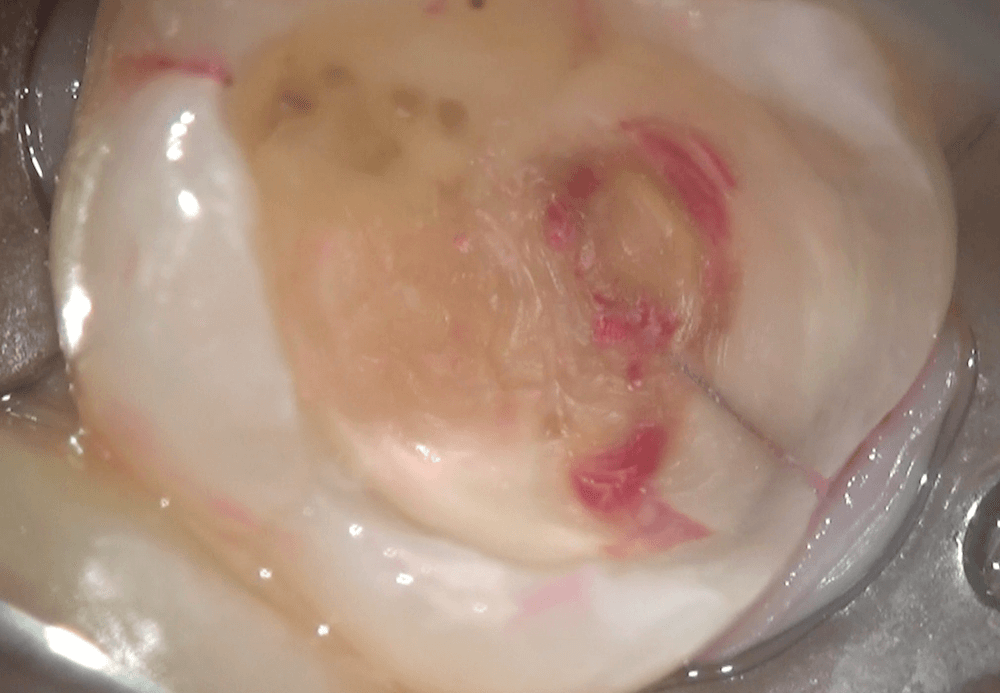

実際の治療を提示致します。麻酔をして、つめものを取り除き、内部をみると、柔らかく、

ボソボソしています。これが虫歯です。

さらに虫歯を取り除き、

虫歯が残っている部分を染め出します。また、ヒビが入っているのがわかりました。